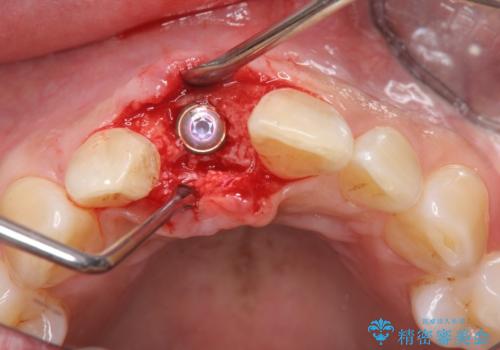

審美的・機能的に良好な位置に埋入するには、骨量が十分ではなかったため骨の造成を併用したインプラント埋入外科手術を行います。

前歯のインプラントを審美的に仕上げるには、インプラント周囲に十分な骨の量と厚みのある歯肉、そして埋入位置の精密な位置付けが重要です。